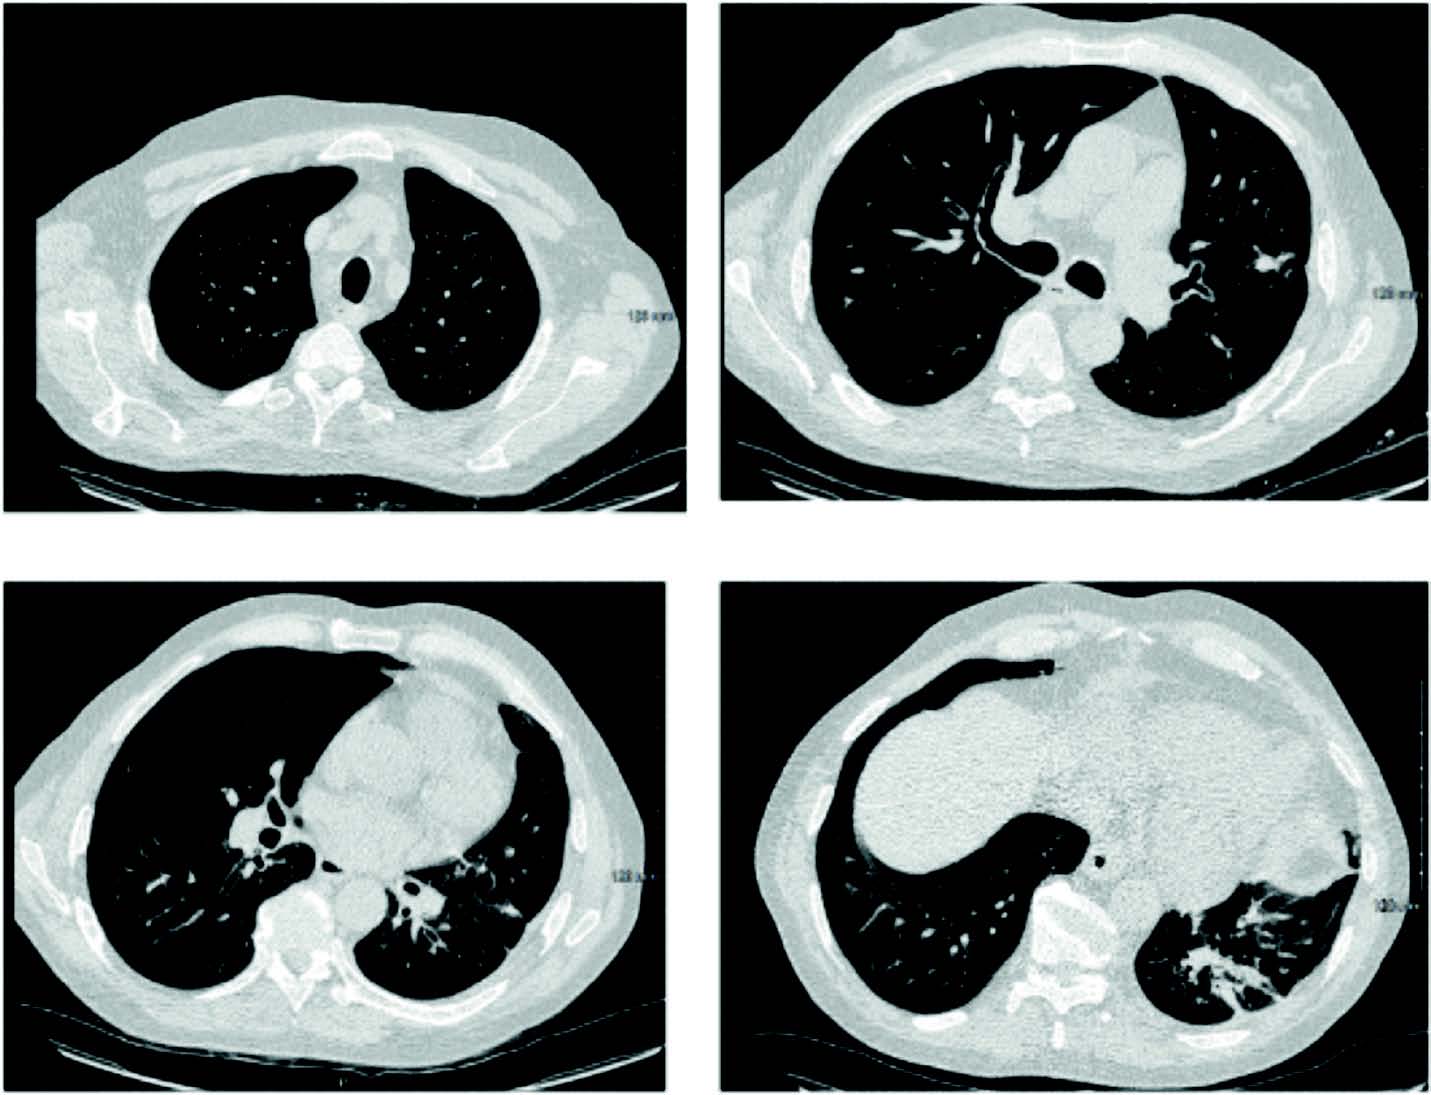

À 18 mois de l'épisode aiguë, le patient est en rémission hématologique, en excellent état général (PS 0), et asymptomatique sur le plan respiratoire ; seule persiste une séquelle excavée lobaire inférieure gauche et un nodule sous-pleural lobaire supérieur gauche non évolutif (figure 3) et non métabolique en 18FDG TEP-TDM.

Figure 3. Scanner thoracique après 2 ans de traitement

Pour notre patient, la question en suspens est la place de la chirurgie des lésions résiduelles notamment dans la perspective d'un éventuel traitement immunosuppresseur en cas de réaction du greff on contre l'hôte chronique (c-GVHD). La chirurgie reste à l'état de discussion devant l'absence d'immunosuppresseur, la non évolutivité scanographique sans activité métabolique en TEP chez un patient asymptomatique mais ces lésions incitent la poursuite du posaconazole en monothérapie compte tenu de l'immunosuppression post ACSH.